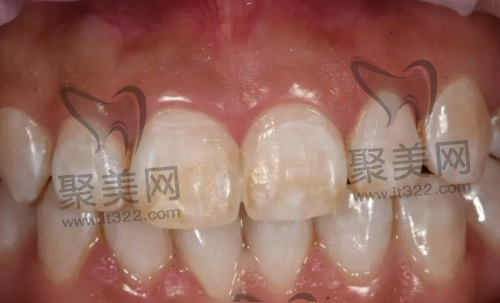

氟斑牙形成的主要原因就是氟元素摄入过多,大多数情况下就是饮用含氟量较多的水,也有小孩刷牙时会吞咽含氟牙膏的原因,主要症状就是牙齿颜色的变化,不及时治疗会造成牙釉质的损伤。

氟斑牙牙齿颜色变化在表面,会出现白粉笔块状的颜色,主要是恒牙会产生氟斑牙,乳牙基本上不会出现在何种情况。